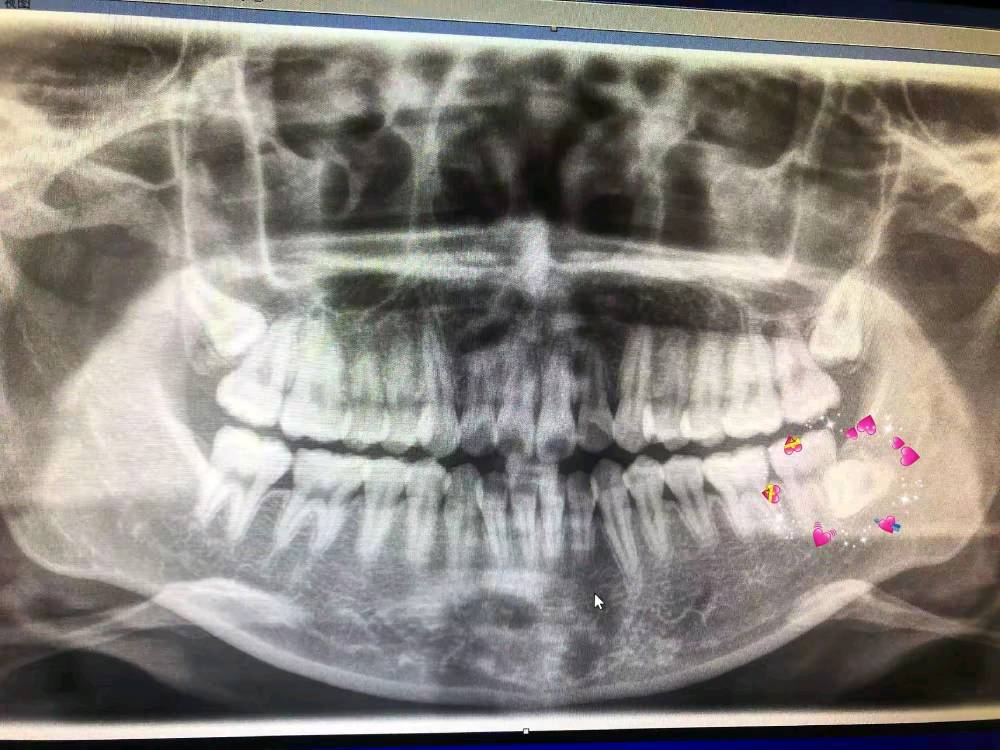

再来展示一张牙齿在颌骨里是如何错落而并非一排的,上颌的两颗智齿也是实在没地方了就干脆躺下了,而且是里外躺。

我们手术要谈啊,可能也是唯一能够让患者重视一点的,这个下牙槽神经的损伤问题啊。